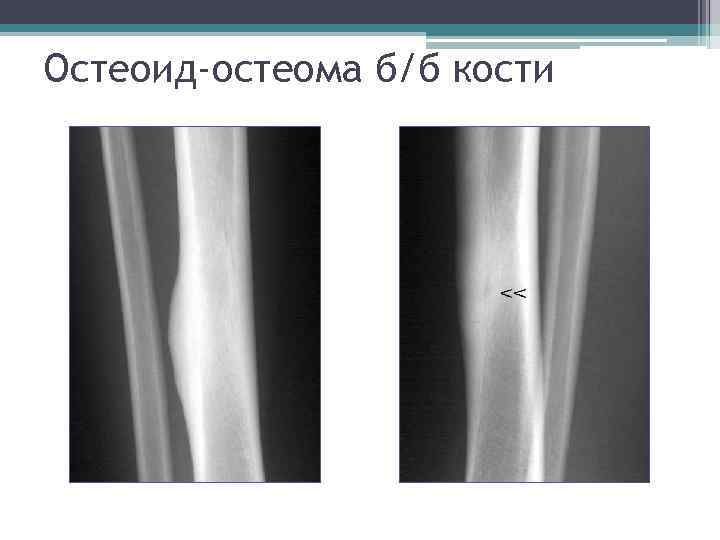

Остеоид-остеома • Частота - 4 - 10% • Поражаемый возраст - 20 -30 лет. • Излюбленная локализация - большеберцовая и малоберцовая кости, задние элементы позвонков. • Клиника – интенсивные ночные боли.

Особая примета • Главный рентгеновский признак – мелкий (диаметром несколько мм) участок деструкции, который окружен выраженным склеротическим процессом. • На жаргонном языке её называют – «пуговкой»

Остеоид-остеома б/б кости

Остеоид-остеома головки бедра